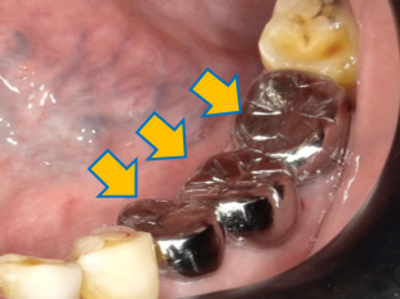

口腔缺牙的問題:

缺牙的後遺症:蛀牙、鄰牙傾斜、咬合不正(如下方x光片所標示)